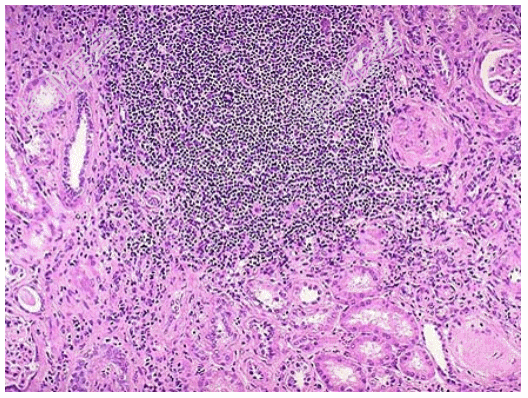

- [材料题] 患者女性,53岁,双肾缩小,表面可见不规则瘢痕,两侧改变不对称,切开,皮髓质界限不清,肾乳头萎缩,肾盏和肾盂因瘢痕收缩而变形,肾盂黏膜粗糙;巨检如图,镜下如图所示。